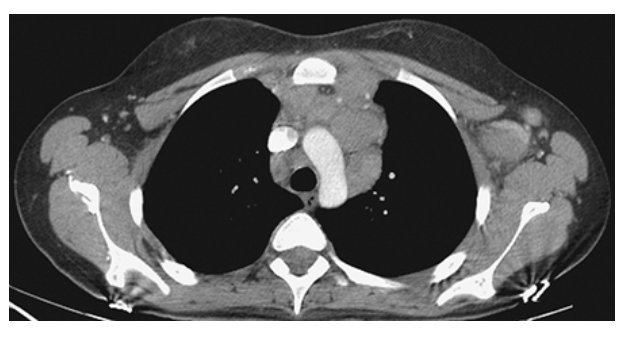

Hodgkin Disease. Contrast-enhanced CT shows a very large anterior mediastinal mass displacing the aortic arch posteriorly and compressing the trachea. This mediastinal mass in this young patient is consistent with lymphoma or Hodgkin disease.

Hodgkin Disease. Axial CECT of the chest shows bulky anterior mediastinal and left axillary lymphadenopathy in this patient with Hodgkin lymphoma.

Hodgkin Disease. Axial CECT of the chest shows the congolomeration of nodes extending down and appearing as an anterior mediastinal mass.